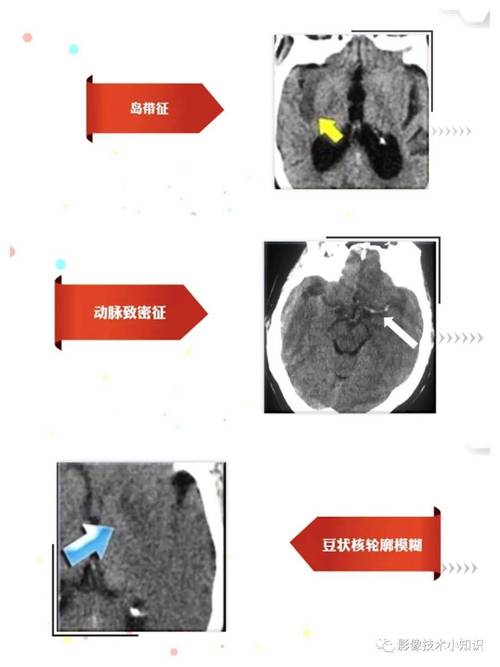

- CT(计算机断层扫描):对于急性脑梗塞,CT在发病后的最初几个小时(通常是6小时内),通常是完全正常的,这是因为脑组织在缺血的早期,其结构密度还没有发生明显改变,CT无法探测到这种细微的变化。

- 6-24小时:部分患者的CT开始显示一些间接征象,如脑沟变浅、脑白质密度轻微降低。

- 24-48小时后:绝大多数脑梗塞患者的CT上会显示出明确的低密度梗塞灶,这时,CT的诊断价值就大大提高了。